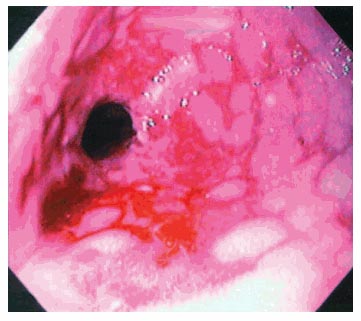

GradeII: Çatlak şeklinde çizgisel erezyonlar